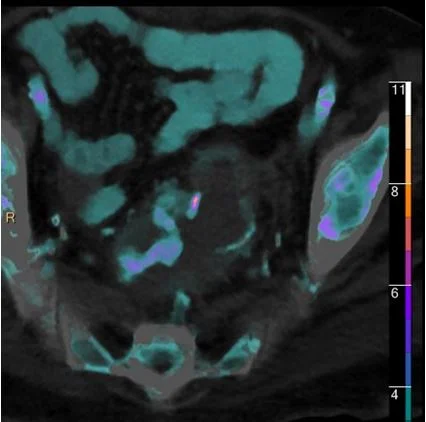

Iodine map: Confirms bleeder arising from near the anastomosis

Iodine overlay: Nicely confirms findings